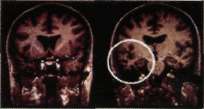

Wernicke tipi afazisi olan bir hastada nükleer

manyetik görüntüleme ile sol şakak lobunda atrofi

(beyaz daire içindeki siyahlık). Hasta duyduğu veya

okuduğu sözcükleri anlamıyor, gördüğü cisimlere

anlam veremiyordu. Söylenen sözleri tekrar

edemiyor, gördüğü cisimlerin ismini

söyleyemiyordu. Beyninde dejeneratif bir sinir

hastalığı vardır.